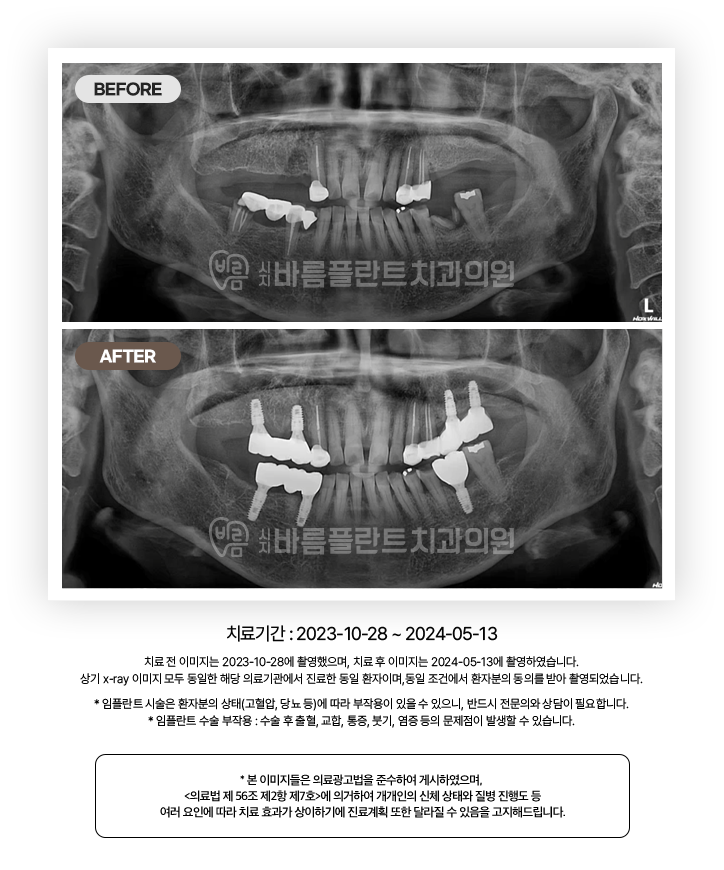

임플란트 CASE